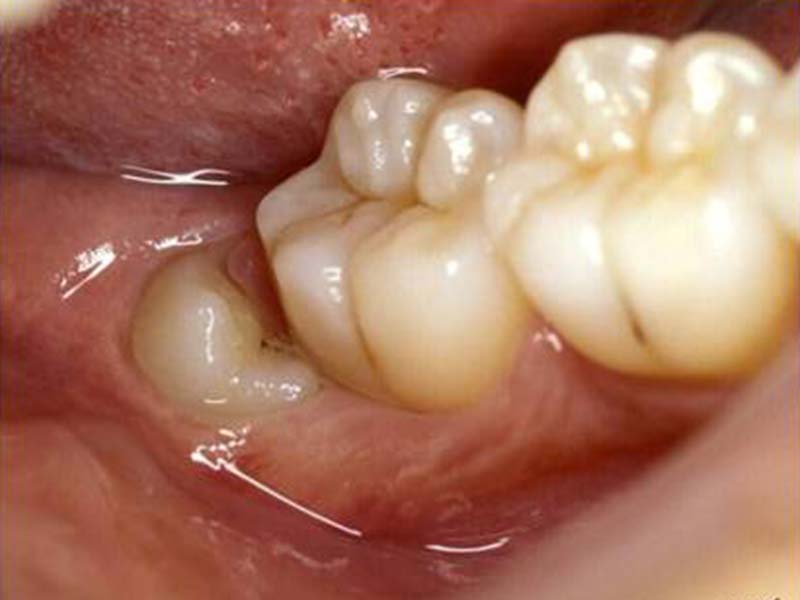

智齒手術

• 智齒手術